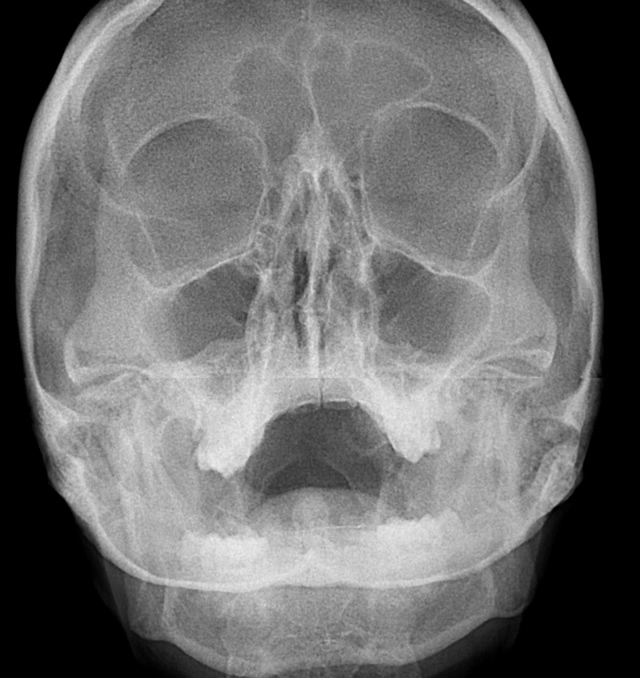

Proyección de Caldwell. La radiografía de Caldwell ( Caldwell's view en inglés) o también llamada radiografía postero-anterior (PA) de senos paranasales, es una proyección radiológica específica para la visualización de los senos frontales y etmoidales. 1 Los pacientes con sospecha de sinusitis frontal (cefalea frontal predominante.

Proyección de Cadwell. Diccionario médico. Proyección radiológica para el estudio del macizo facial, también denominada frontonaso placa, de utilidad en la valoración de los senos frontoetmoidales. QUIERO ESTAR INFORMADO. La información proporcionada en este Diccionario Médico de la Clínica Universidad de Navarra tiene como objetivo.

Citation, DOI, disclosures and article data. The Caldwell view is a caudally angled radiograph, with its posteroanterior projection allowing for minimal radiation to the orbits. This view may be used in imaging of the skull or facial bones depending on the clinical indications.

RX1 CADWELL. La radiografía de Caldwell o también llamada radiografía postero-anterior (PA) de senos paranasales, es una proyección radiológica específica para la visualización de los senos frontales y etmoidales. Los pacientes con sospecha de sinusitis frontal (cefalea frontal predominante) deben ser dirigidamente estudiados mediante.

Proyección de Caldwell Wikiwand

grupos de senos. Proyección PA axial (Método Cadwell): Senos frontales y etmoidales anteriores. Proyección de Waters (Parietoacantial): con boca cerrada: Senos maxilares Proyección de Waters (Parietoacantial) con boca abierta: Senos maxilares y esfenoidales. Proyección Submentovertical: Senos etmoidal y esfenoidal. Centraje: Línea.

Proyección de Caldwell: proyección AP de los senos paranasales en flexión de la cabeza, placa entre. Proyeccion lateral: imagen del plano sagital del paciente. 3. Indicación. -Trauma facial. -Actualmente la radiografía simple de cavidades paranasales no se recomienda para el estudio de sinusitis aguda, ya que su diagnóstico es clínico. 4.